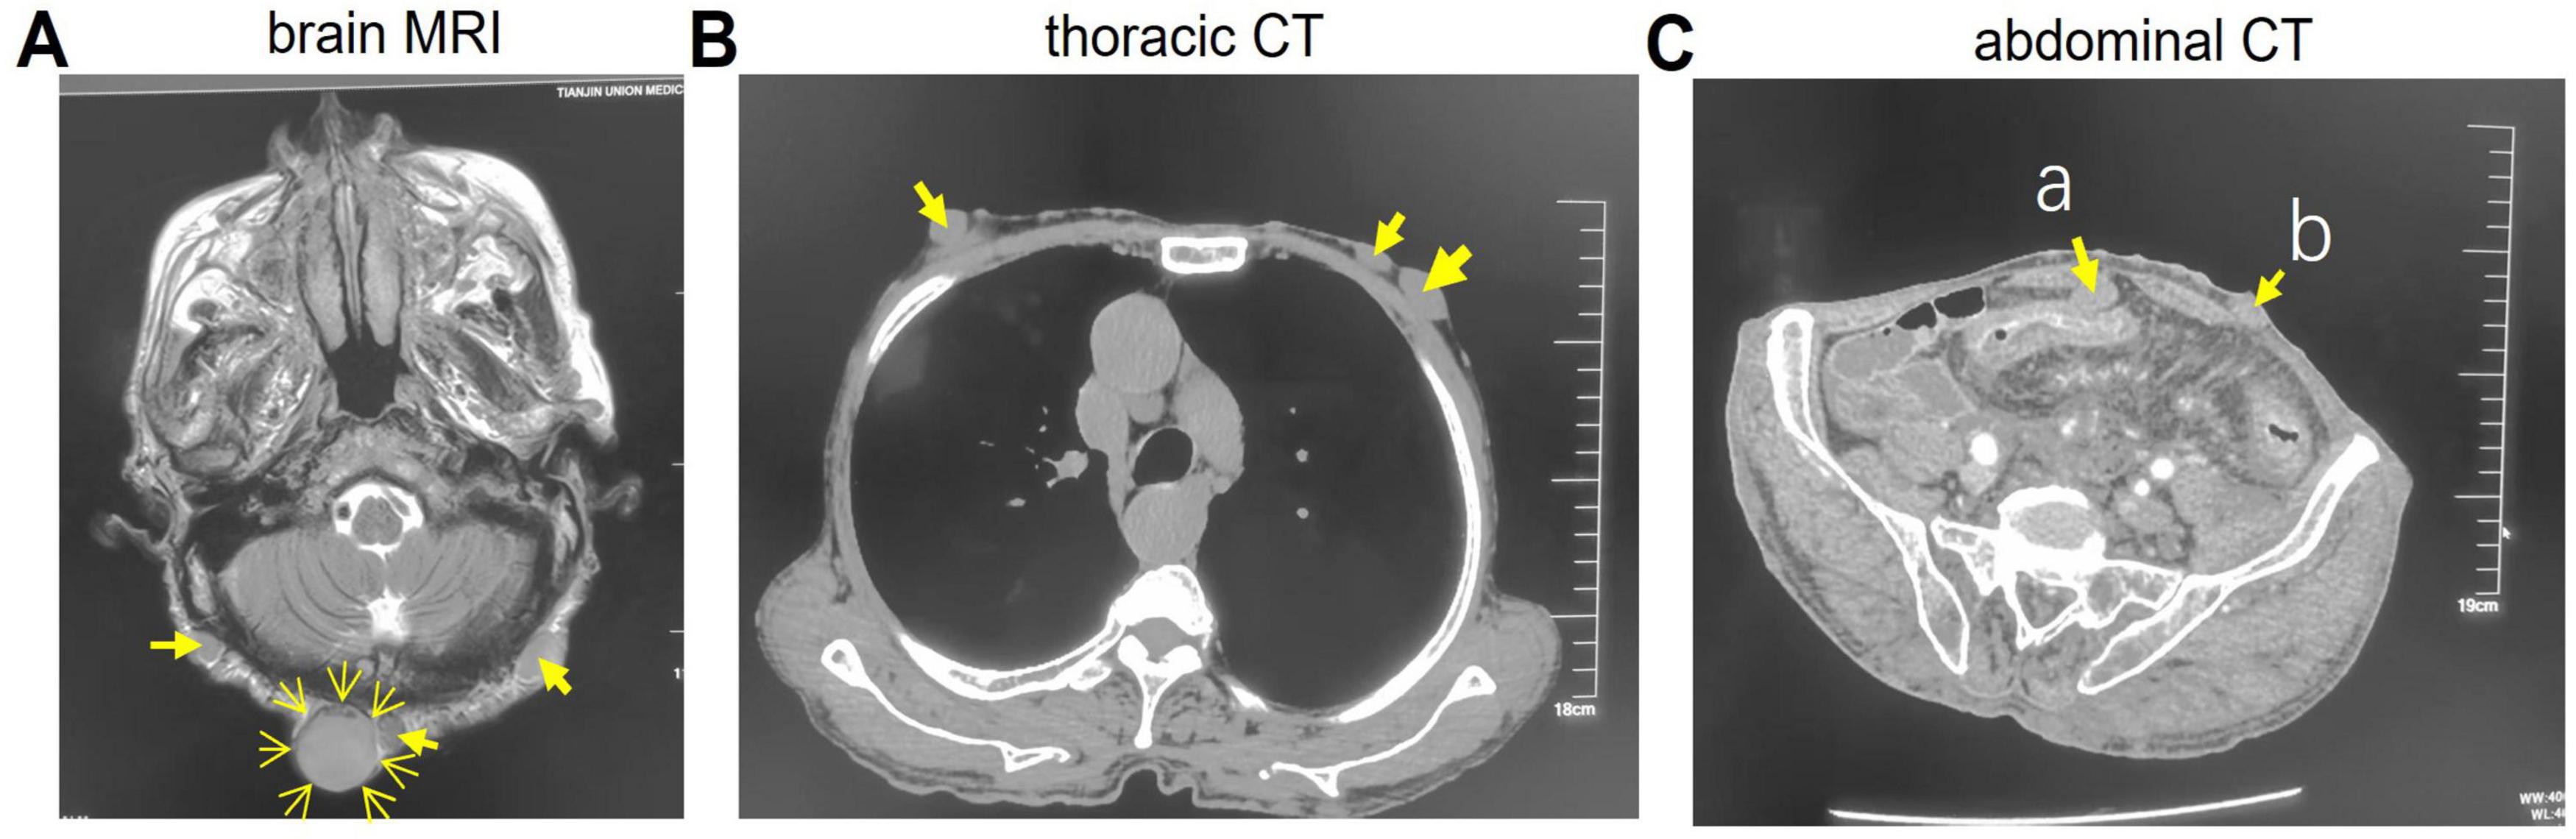

FIGURE 4

Imaging studies data. (A) Brain magnetic resonance imaging (MRI). (B) Thoracic CT. (C) Abdominal CT. The arrows indicate nodules. a, Omentum nodule; b, Abdominal nodule.

Thoracic CT (Figure 4B) revealed multiple subcutaneous nodules in the chest wall and back (arrows). Abdominal CT (Figure 4C) demonstrated diffuse circumferential wall thickening in the descending colon, sigmoid colon, and rectum, with loss of haustral folds, consistent with ulcerative colitis. Multiple nodules were also present in the omentum (arrow a), abdominal (arrow b) and pelvic walls, lumbar region, buttocks, and perineal subcutaneous tissue. Enlarged lymph nodes were noted in the para-aortic and superior rectal artery regions, possibly indicating inflammation or lymphadenopathy.